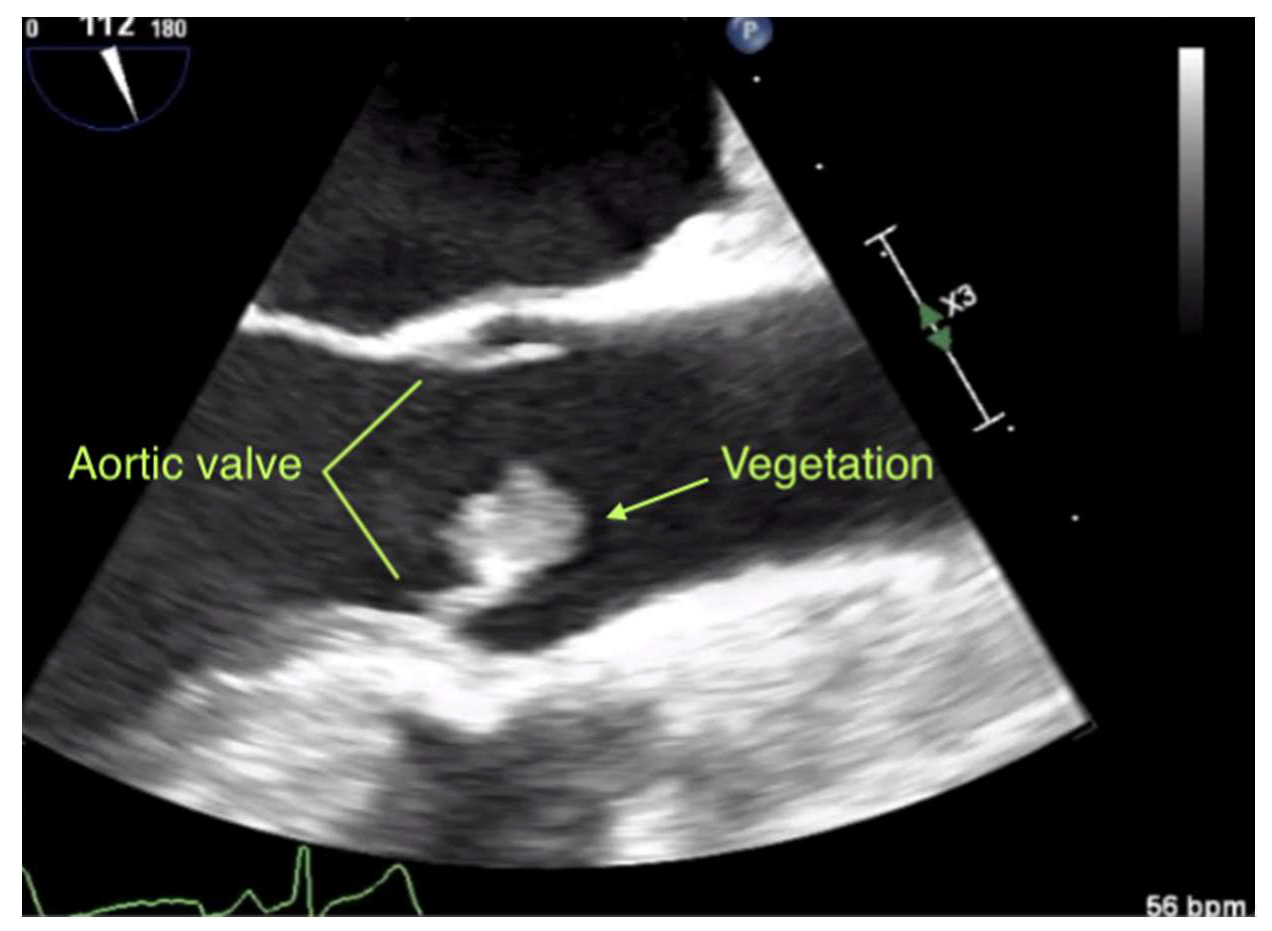

Six weeks later, TEE demonstrated a sudden progressive growth of the vegetation to 12 × 12 × 10 mm3 and new moderate aortic insufficiency (Figure 2; Supplementary Video S1). Due to the lack of regression, a more complex bleeding disorder seemed unlikely.

Figure 2.

Ultrasound video (still). Transesophageal echocardiography performed in the long-axis view at midesophageal level. A visible echogenic mass, consistent with a vegetation of 12 × 12 × 10 mm3 adhered to the native aortic valve.